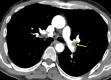

Pulmonary embolism (PE) is a serious condition that often poses a diagnostic challenge. We report a case of a 57-year-old man with tobacco dependence who presented with multiple trauma, with chest imaging findings concerning for malignancy. While performing bronchoscopy with endobronchial ultrasound (EBUS), an echogenic material was incidentally found in the left pulmonary artery. Computed tomography pulmonary angiography (CTPA) was immediately obtained and confirmed the diagnosis of PE. This case illustrates the utility of routine pulmonary artery examination during EBUS procedures in patients at risk of PE and the importance of prompt management including confirmation with CTPA.